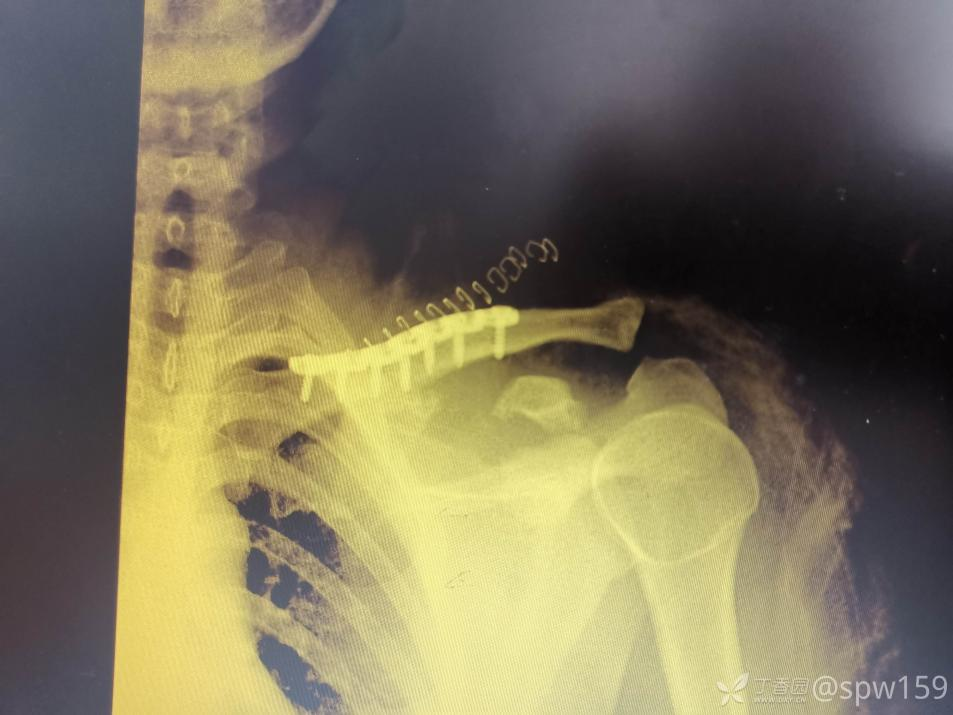

锁骨骨折大家一定都觉得很简单,但锁骨骨折也有一个并不少见的坑,看看下面的病例:

这个锁骨骨折简单吗?简单!做不就完了吗?

做完了,骨折解剖复位漂亮吧?干得漂亮!等等!怎么肩锁关节脱位了 ……

这个锁骨骨折简单吗?另一位网友分享:

等下,拍个双侧对比看看,锁骨骨折合并肩锁关节脱位,还好术前发现了 ……

这样的病例少吗?还真不少,一搜一大把!

6.8% 的锁骨中段骨折患者伴有同侧肩锁关节脱位。这个坑也不能踩啊!